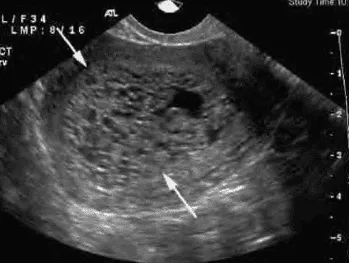

Phần tiêu đề “Cận lâm sàng”Siêu âm:

Hình ảnh “Siêu âm thai trứng toàn phần”.

- Thai trứng toàn phần: “tổ ong”/“bão tuyết” không thấy phôi, hình ảnh nhiều nang nước.